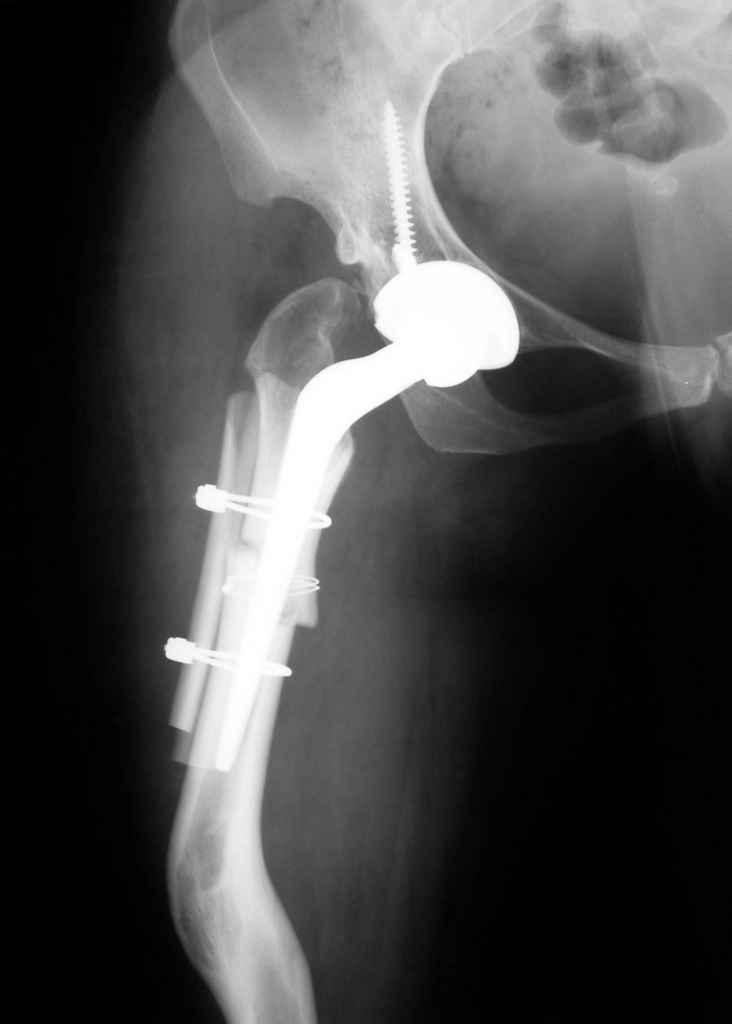

Moghno i tak kak sdelali my: pelvic support + tibial and equinus correction .

Слайд 1

Слайд 2

Слайд 3

Слайд 4

Devushka predstavlennaya na snimke nachala s LLD 9 cm, valgus deformation of the tibia, huge Trendelenburg( vidno na snimke).

Seichas : no LLD ,no Trendelenburg, reasonable hip motion.A samoe glavnoe ei ne predstoit kaghdye 10-15 let delat revision THR.

Уважаемый коллега! Не смогла не присоединиться к дискуссии, так как она стала непосредственно касаться опорных остеотомий, разработанных и широко применявшихся в нашем Центре - РНЦ "ВТО" им. академика Г.А.Илизарова в 80-90 годы. Следует отметить, что демонстрируемые примеры выполнения опорных остеотомий свидетельствуют о "незнании" врачами технических особенностей их выполнения. Проксимальная остеотомия должна быть выполнена на меж- или подвертельном уровне, но никак не на границе верхней и средней трети бедра, не требуется также такое громадное отведение промежуточного фрагмента, а, следовательно, не нужен и такой противоразворот на дистракционном регенерате.